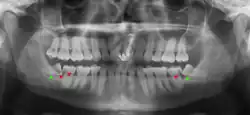

Impacted wisdom teeth are classified by their direction of impaction, their depth compared to the biting surface of adjacent teeth and the amount of the tooth's crown that extends through gum tissue or bone. Impacted wisdom teeth can also be classified by the presence or absence of symptoms and disease. Screening for the presence of wisdom teeth often begins in late adolescence when a partially developed tooth may become impacted. Screening commonly includes a clinical examination as well as x-rays such as panoramic radiographs.

If the tooth cannot be assessed with clinical exam alone, the diagnosis is made using either a panoramic radiograph or cone-beam CT. Where unerupted wisdom teeth still have eruption potential several predictors are used to determine the chance of the teeth becoming impacted. The ratio of space between the tooth crown length and the amount of space available, the angle of the teeth compared to the other teeth are the two most commonly used predictors, with the space ratio being the most accurate. Despite the capacity for movement into early adulthood, the likelihood that the tooth will become impacted can be predicted when the ratio of space available to the length of the crown of the tooth is under 1.[5]: 141